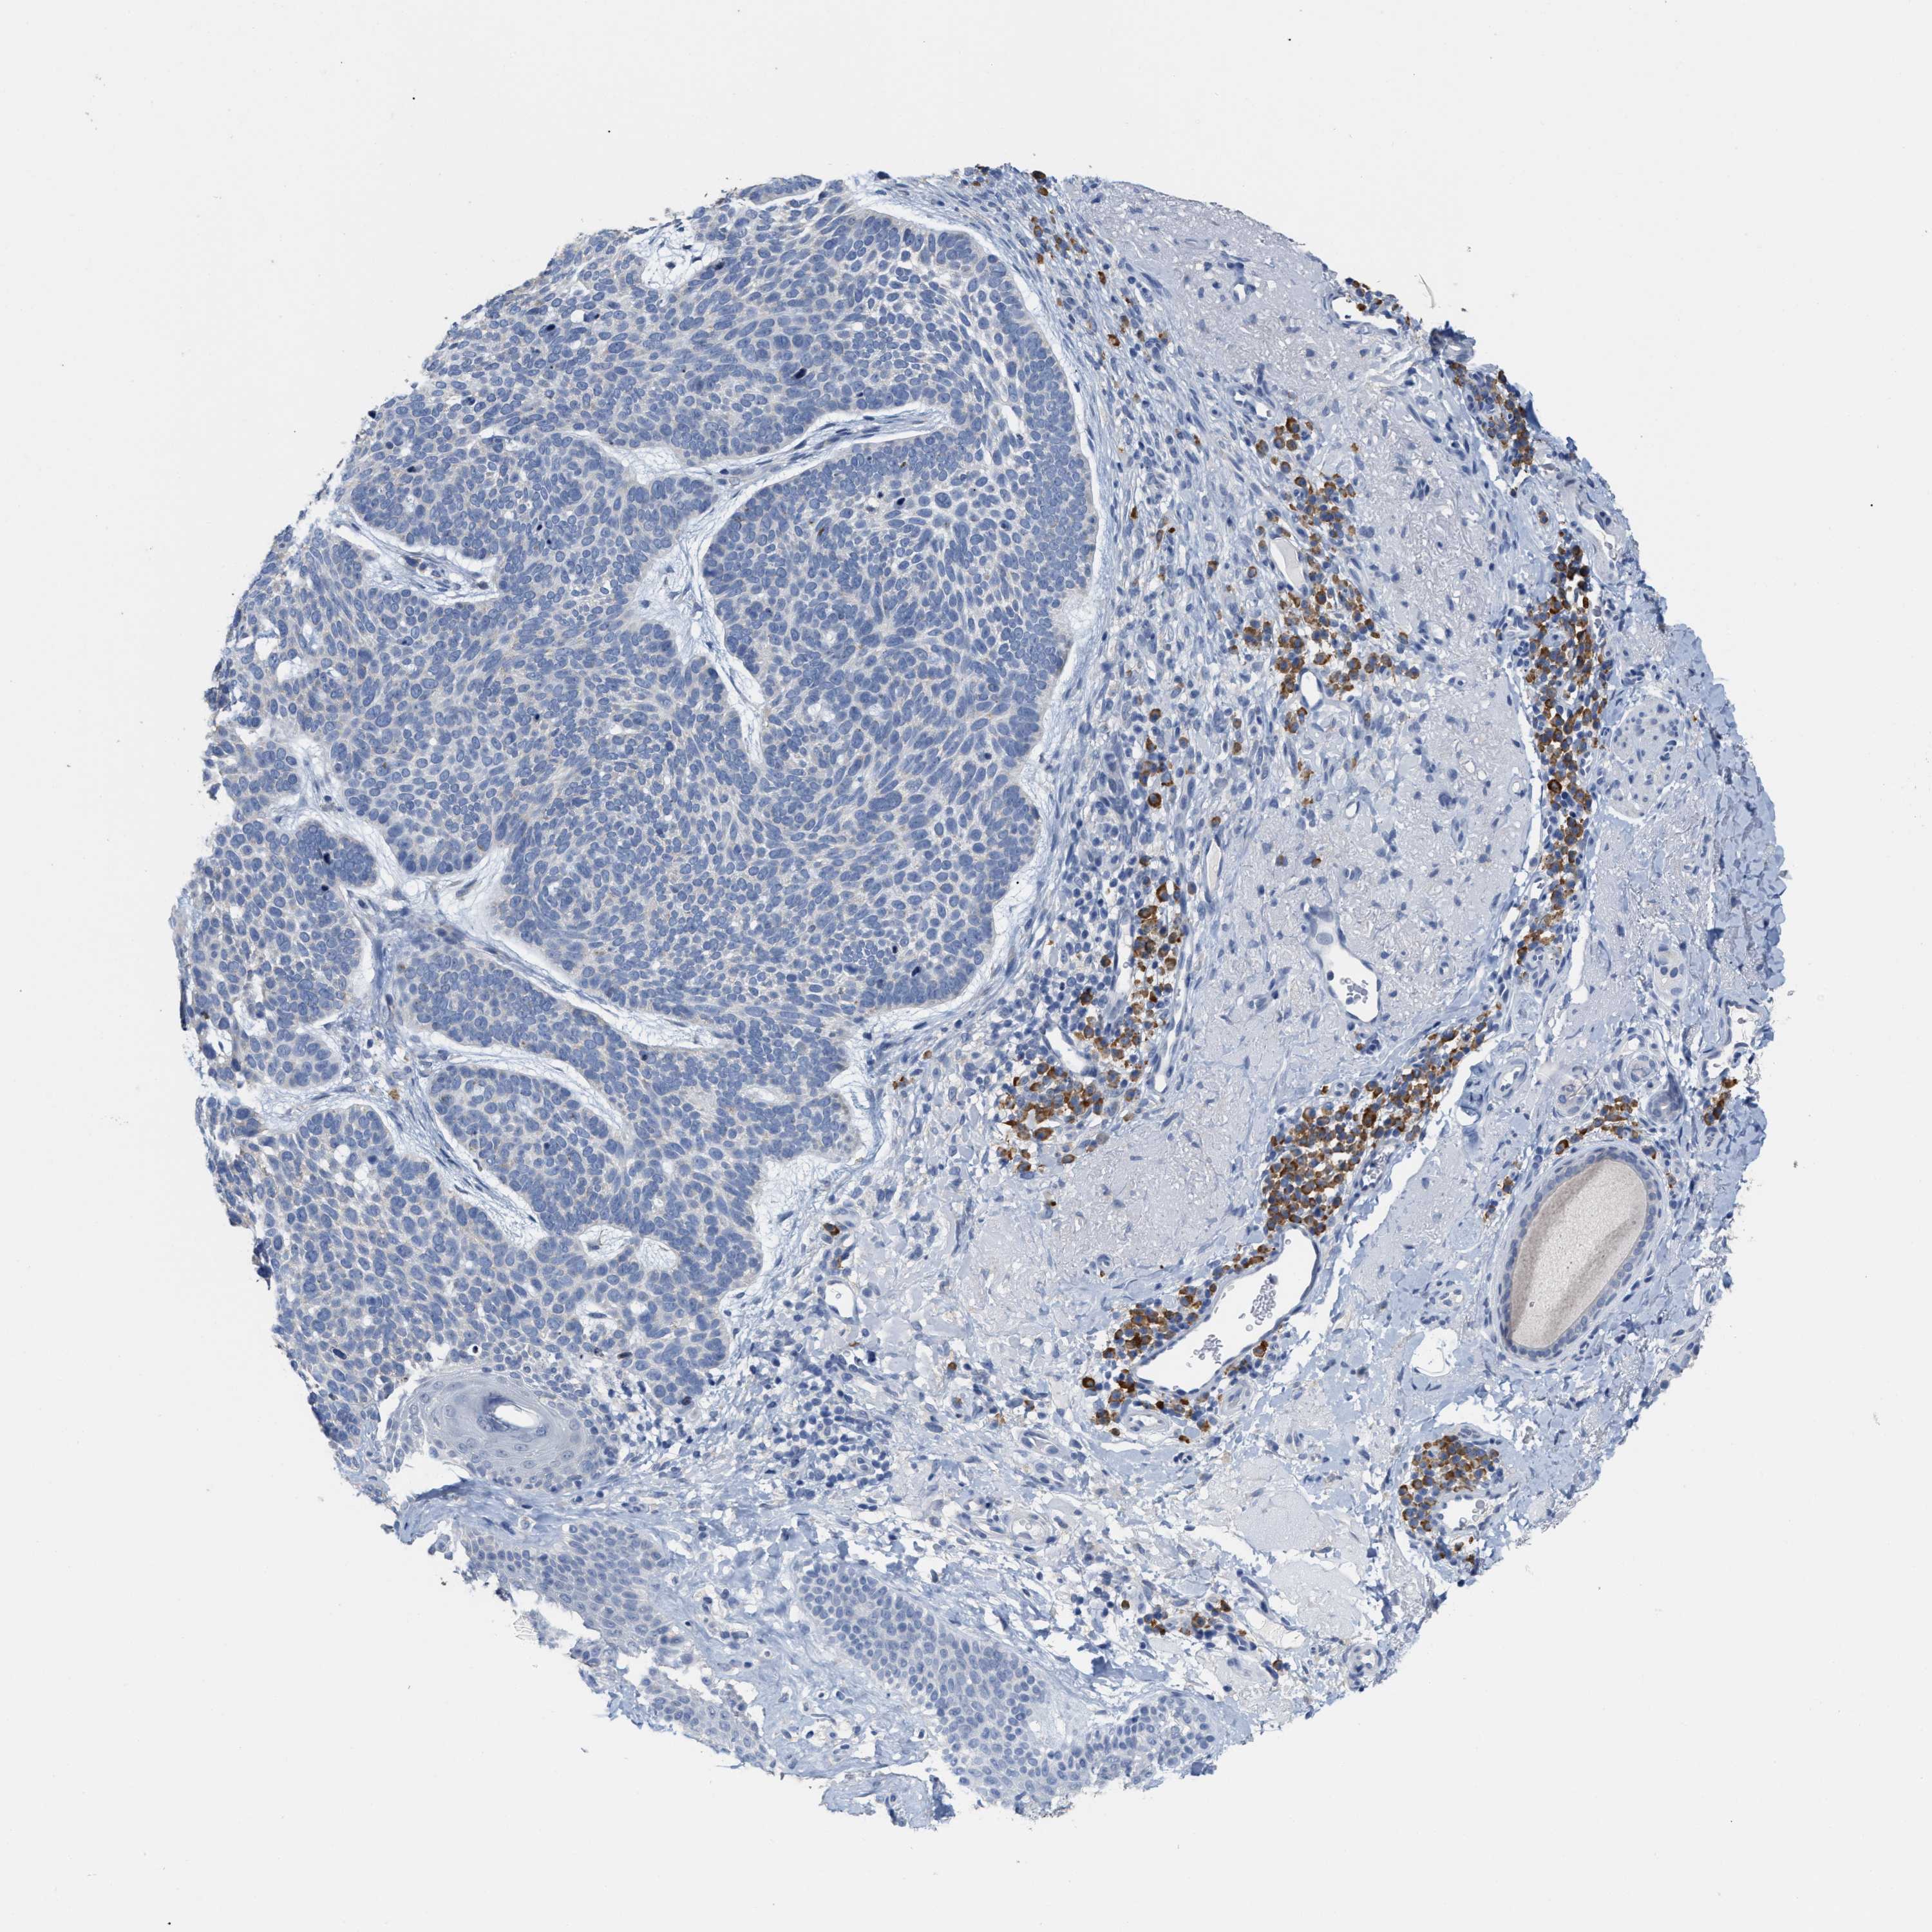

SKIN CANCER - Protein expressioni

A mouse-over function shows sample information and annotation data. Click on an image to view it in a full screen mode. Samples can be filtered based on level of antibody staining by selecting one or several of the following categories: high, medium, low and not detected. The assay and annotation is described here.

Antibody stainingi

Antibody staining in the annotated cell types in the current human tissue is reported as not detected, low, medium, or high, based on conventional immunohistochemistry profiling in selected tissues. This score is based on the combination of the staining intensity and fraction of stained cells.

Each image is clickable and will lead to virtual microscopy that enables deeper exploration of all samples and also displays staining intensity scores, fraction scores and subcellular localization as well as patient and tissue information for each sample.

Antibody HPA020028

Staining

High

Medium

Low

Not detected

Intensity

Strong

Moderate

Weak

Negative

Quantity

>75%

75%-25%

<25%

None

Location

Nuclear

Cytoplasmic/membranous

Cytoplasmic/membranous,nuclear

Basal cell carcinoma

Squamous cell carcinoma, NOS

Squamous cell carcinoma, metastatic, NOS